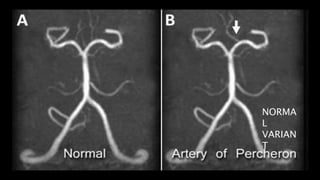

ARTERY OF PERCHERON (AOP)

vascular variant

midbrain and medial thalami

NCCT scans in early acute AOP occlusions are usually normal.

T2/ FLAIR images shows round or ovoid hyperintensities in

the medial thalami, just lateral to 3rd ventricle and midbrain.

• #156 This image shows a single dominant perforating artery fromP1 segment as compared to normal in which multiple small perforating branches supply the thamus and midbrain

• #158 This is a c/o AOP INFARCTION . Axial DWI images shows diffusion restriction in bilateral paramedian thalamic and midbrain region – consistent with acute infarct.